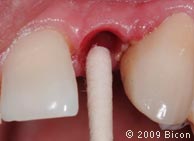

29. Удаление излишков мягких тканей, которые могут препятствовать правильной установке трансфера, производится посредством слепочного римера размером 3 мм, вращаемого вокруг направляющего штифта.

30. Коронка, зацементированная на правом клыке.

31. Подрезка зеленого 3,0 мм трансфера – эта операция позволит избежать соприкосновения с соседними зубами, которое может изменить траекторию движения аналога.

32. Установка пластикового слепочного трансфера в имплантат.